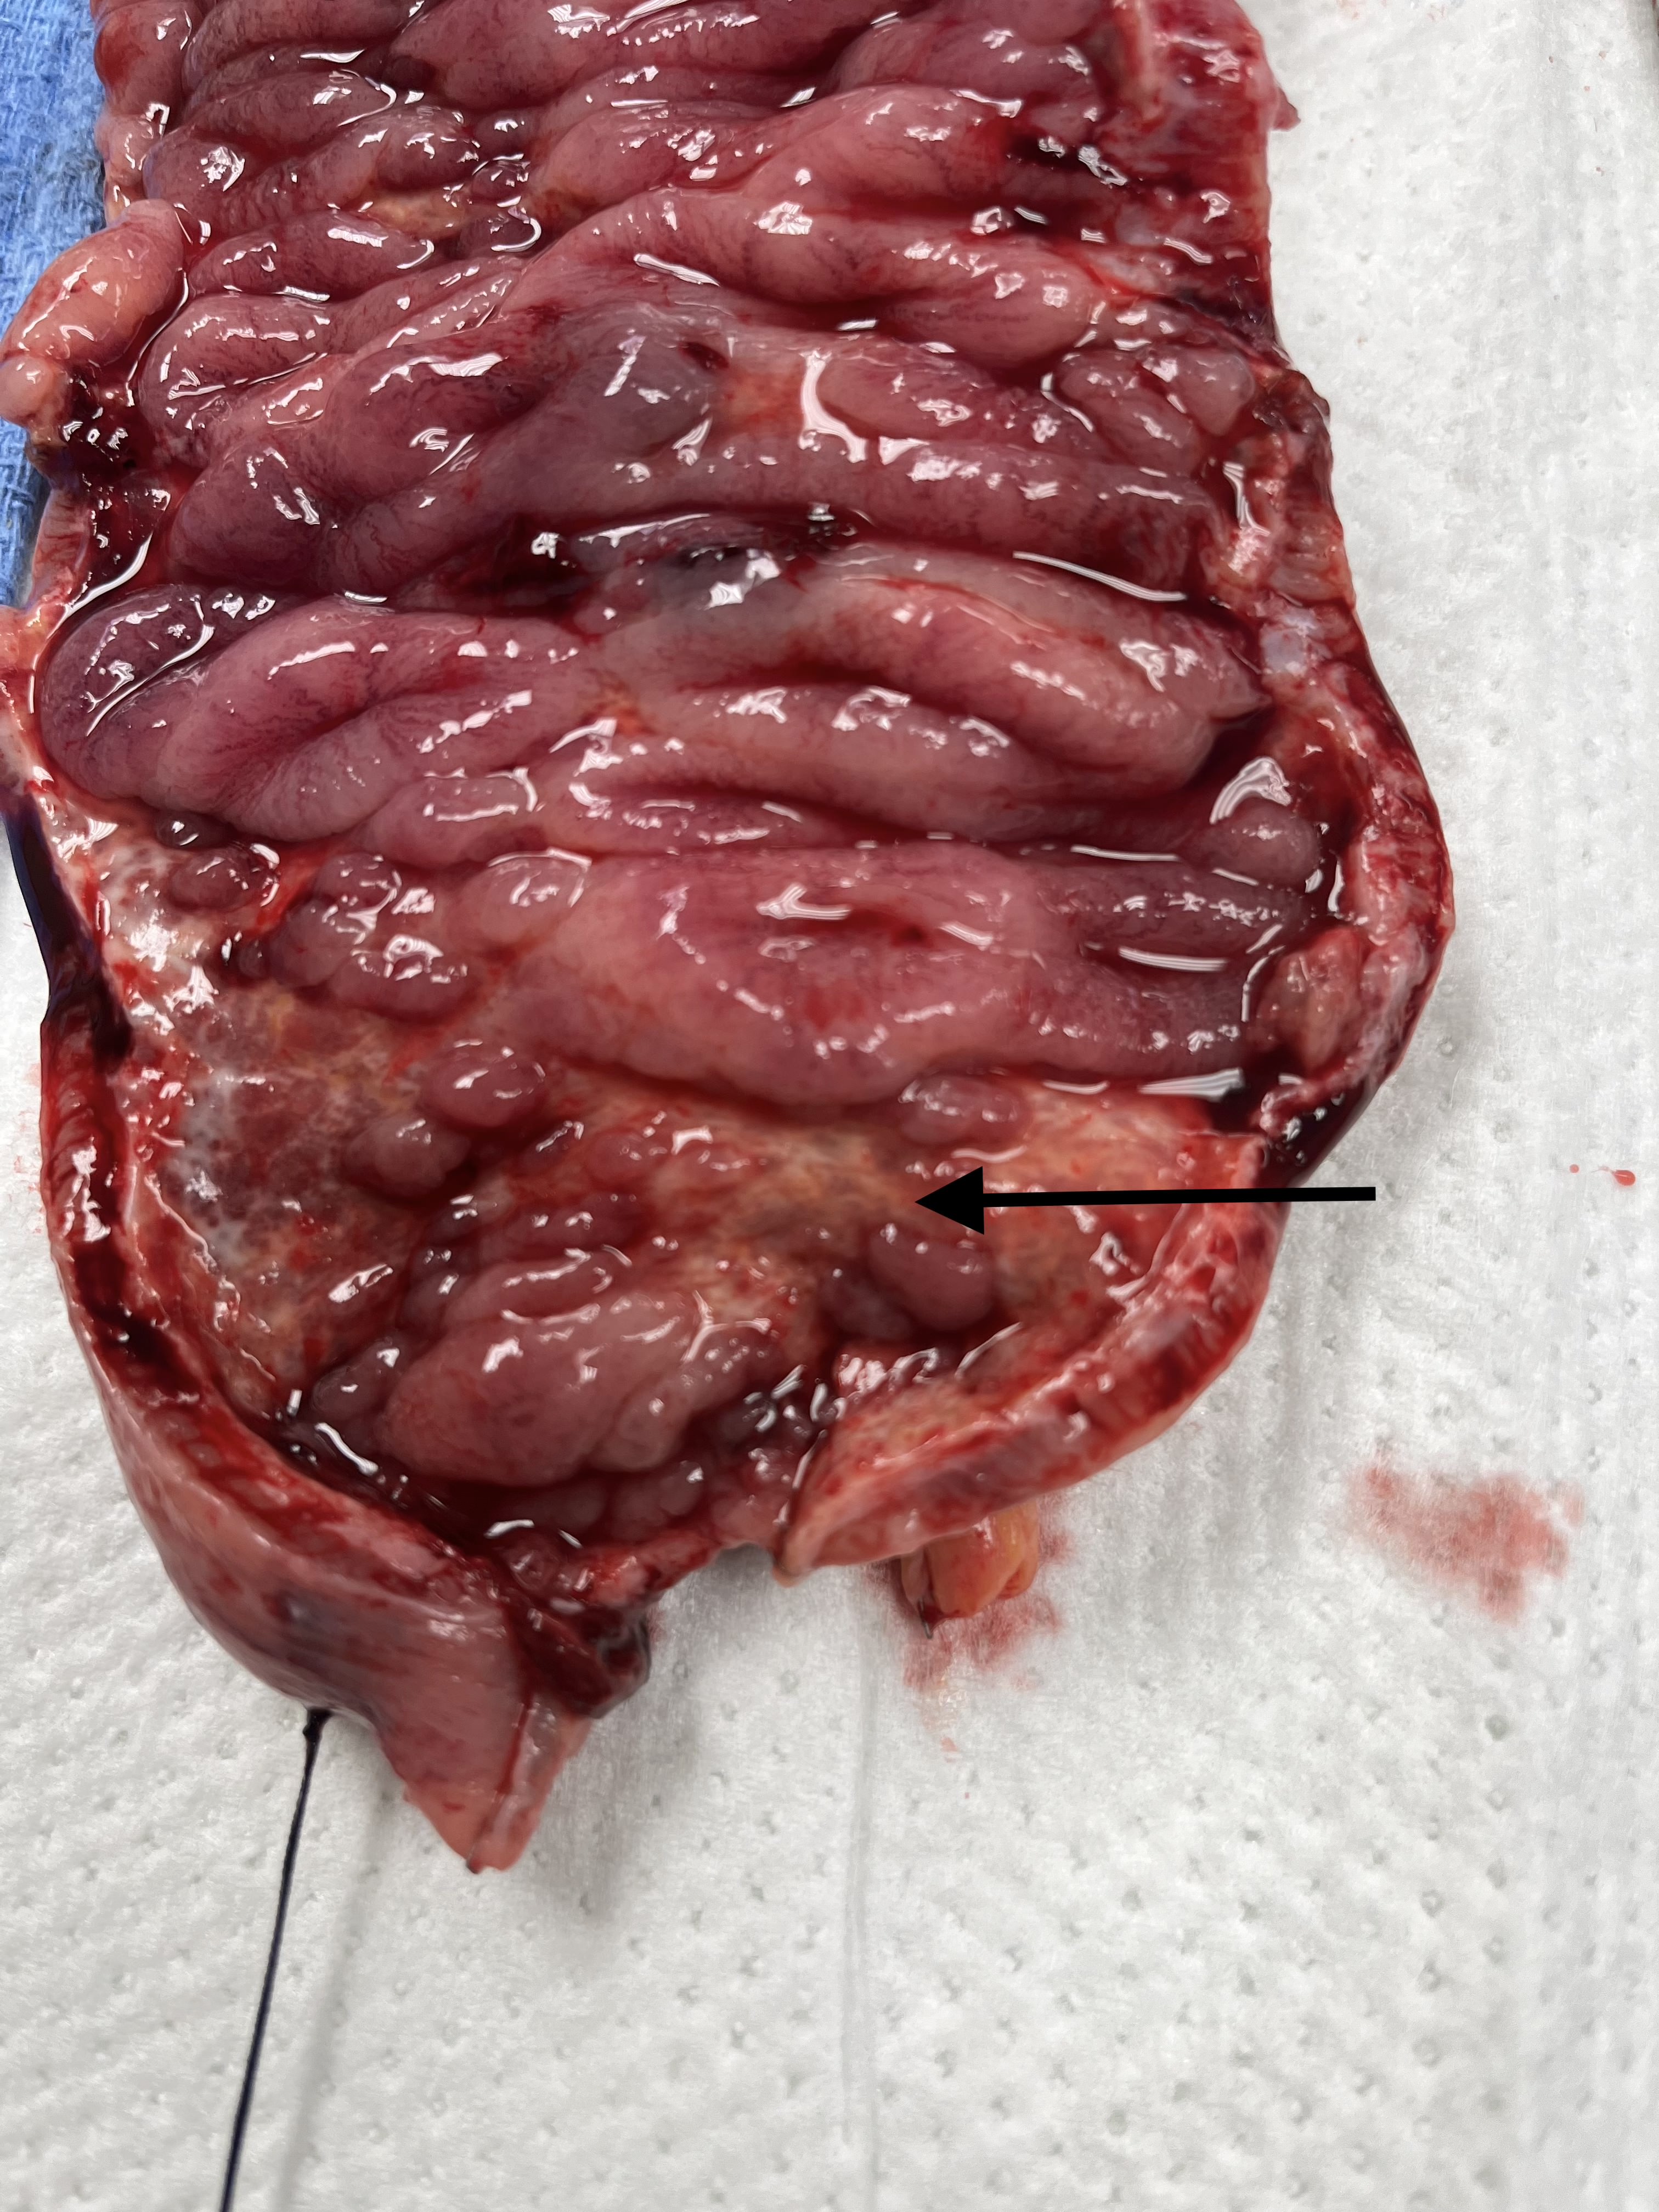

Here we show the deep ulcerations present in the surgical specimen